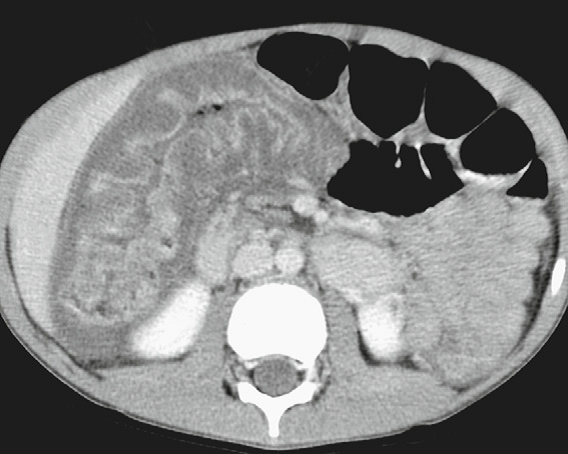

Traumatic pancreatic transection

Fluid (arrowhead) between the pancreas and splenic vein,

a sensitive finding of pancreatic injury.